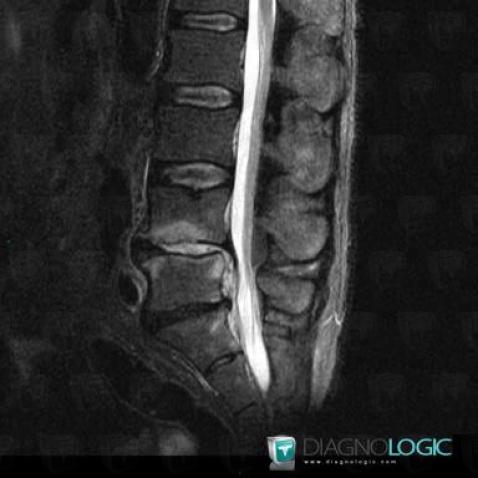

Spondylodiscitis, Vertebral body / Disk, MRI

Here is the specific information in the key image above:

- Diagnosis Spondylodiscitis, Location(s) Vertebral body / Disk, with gamuts Spinal disc lesion, Bone marrow edema